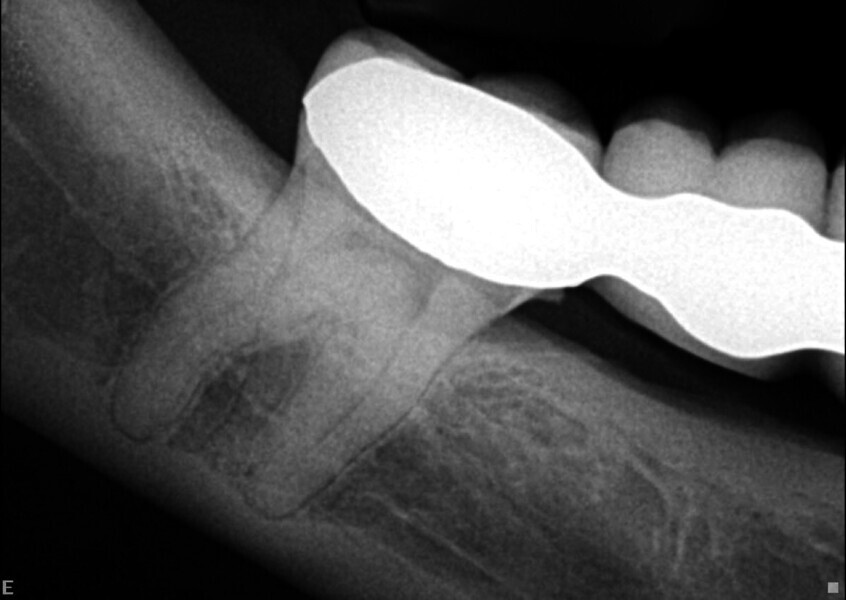

J’ai décidé d’utiliser le système d’imagerie i-CAT, afin de mieux comprendre ce qui se passait. Par comparaison avec la cavité pulpaire de la première molaire, l’examen de la coupe dans le plan horizontal a clairement montré la présence d’une calcification pulpaire de la deuxième molaire (Fig. 2).

Le mode endodontique du nouveau logiciel DTX Studio Clinic permet d’ajouter de nombreuses vues et coupes transversales, ainsi que d’ajuster l’épaisseur des coupes pour vérifier le degré de calcification. Un autre avantage est la possibilité de tracer l’anatomie interne de chacune des racines et de l’ensemble du système, et de sélectionner une couleur pour chaque canal. Cette option est très utile pour examiner l’anatomie interne (Fig. 3).